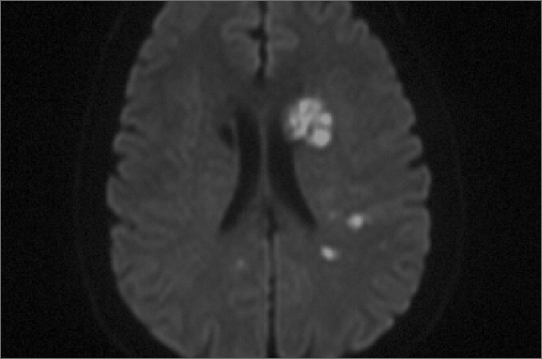

脑核磁共振定性和定量分析(MRI)

- 脑梗死灶的精确定位

- 脑梗死机制分析

- 脑梗死灶的数量、体积测定

- 脑梗死供血血管分析